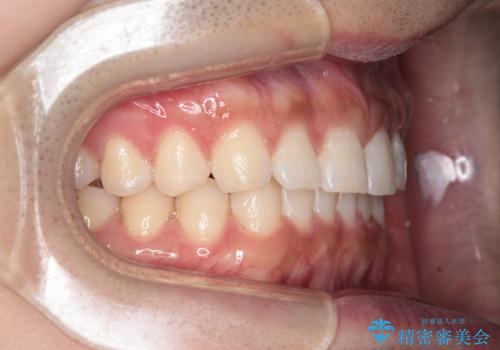

【インビザライン】正中離開を治したい

再矯正ということでがたつきはなくきれいに並んでいましたが、上下のアーチ(歯列弓)の大きさのバランスが悪く、結果的に後戻りの原因になってしまっていました。今回は下のアーチを小さくするためにIPRを行い、かみ合わせのバランスを治しながら前歯の隙間を閉じました。